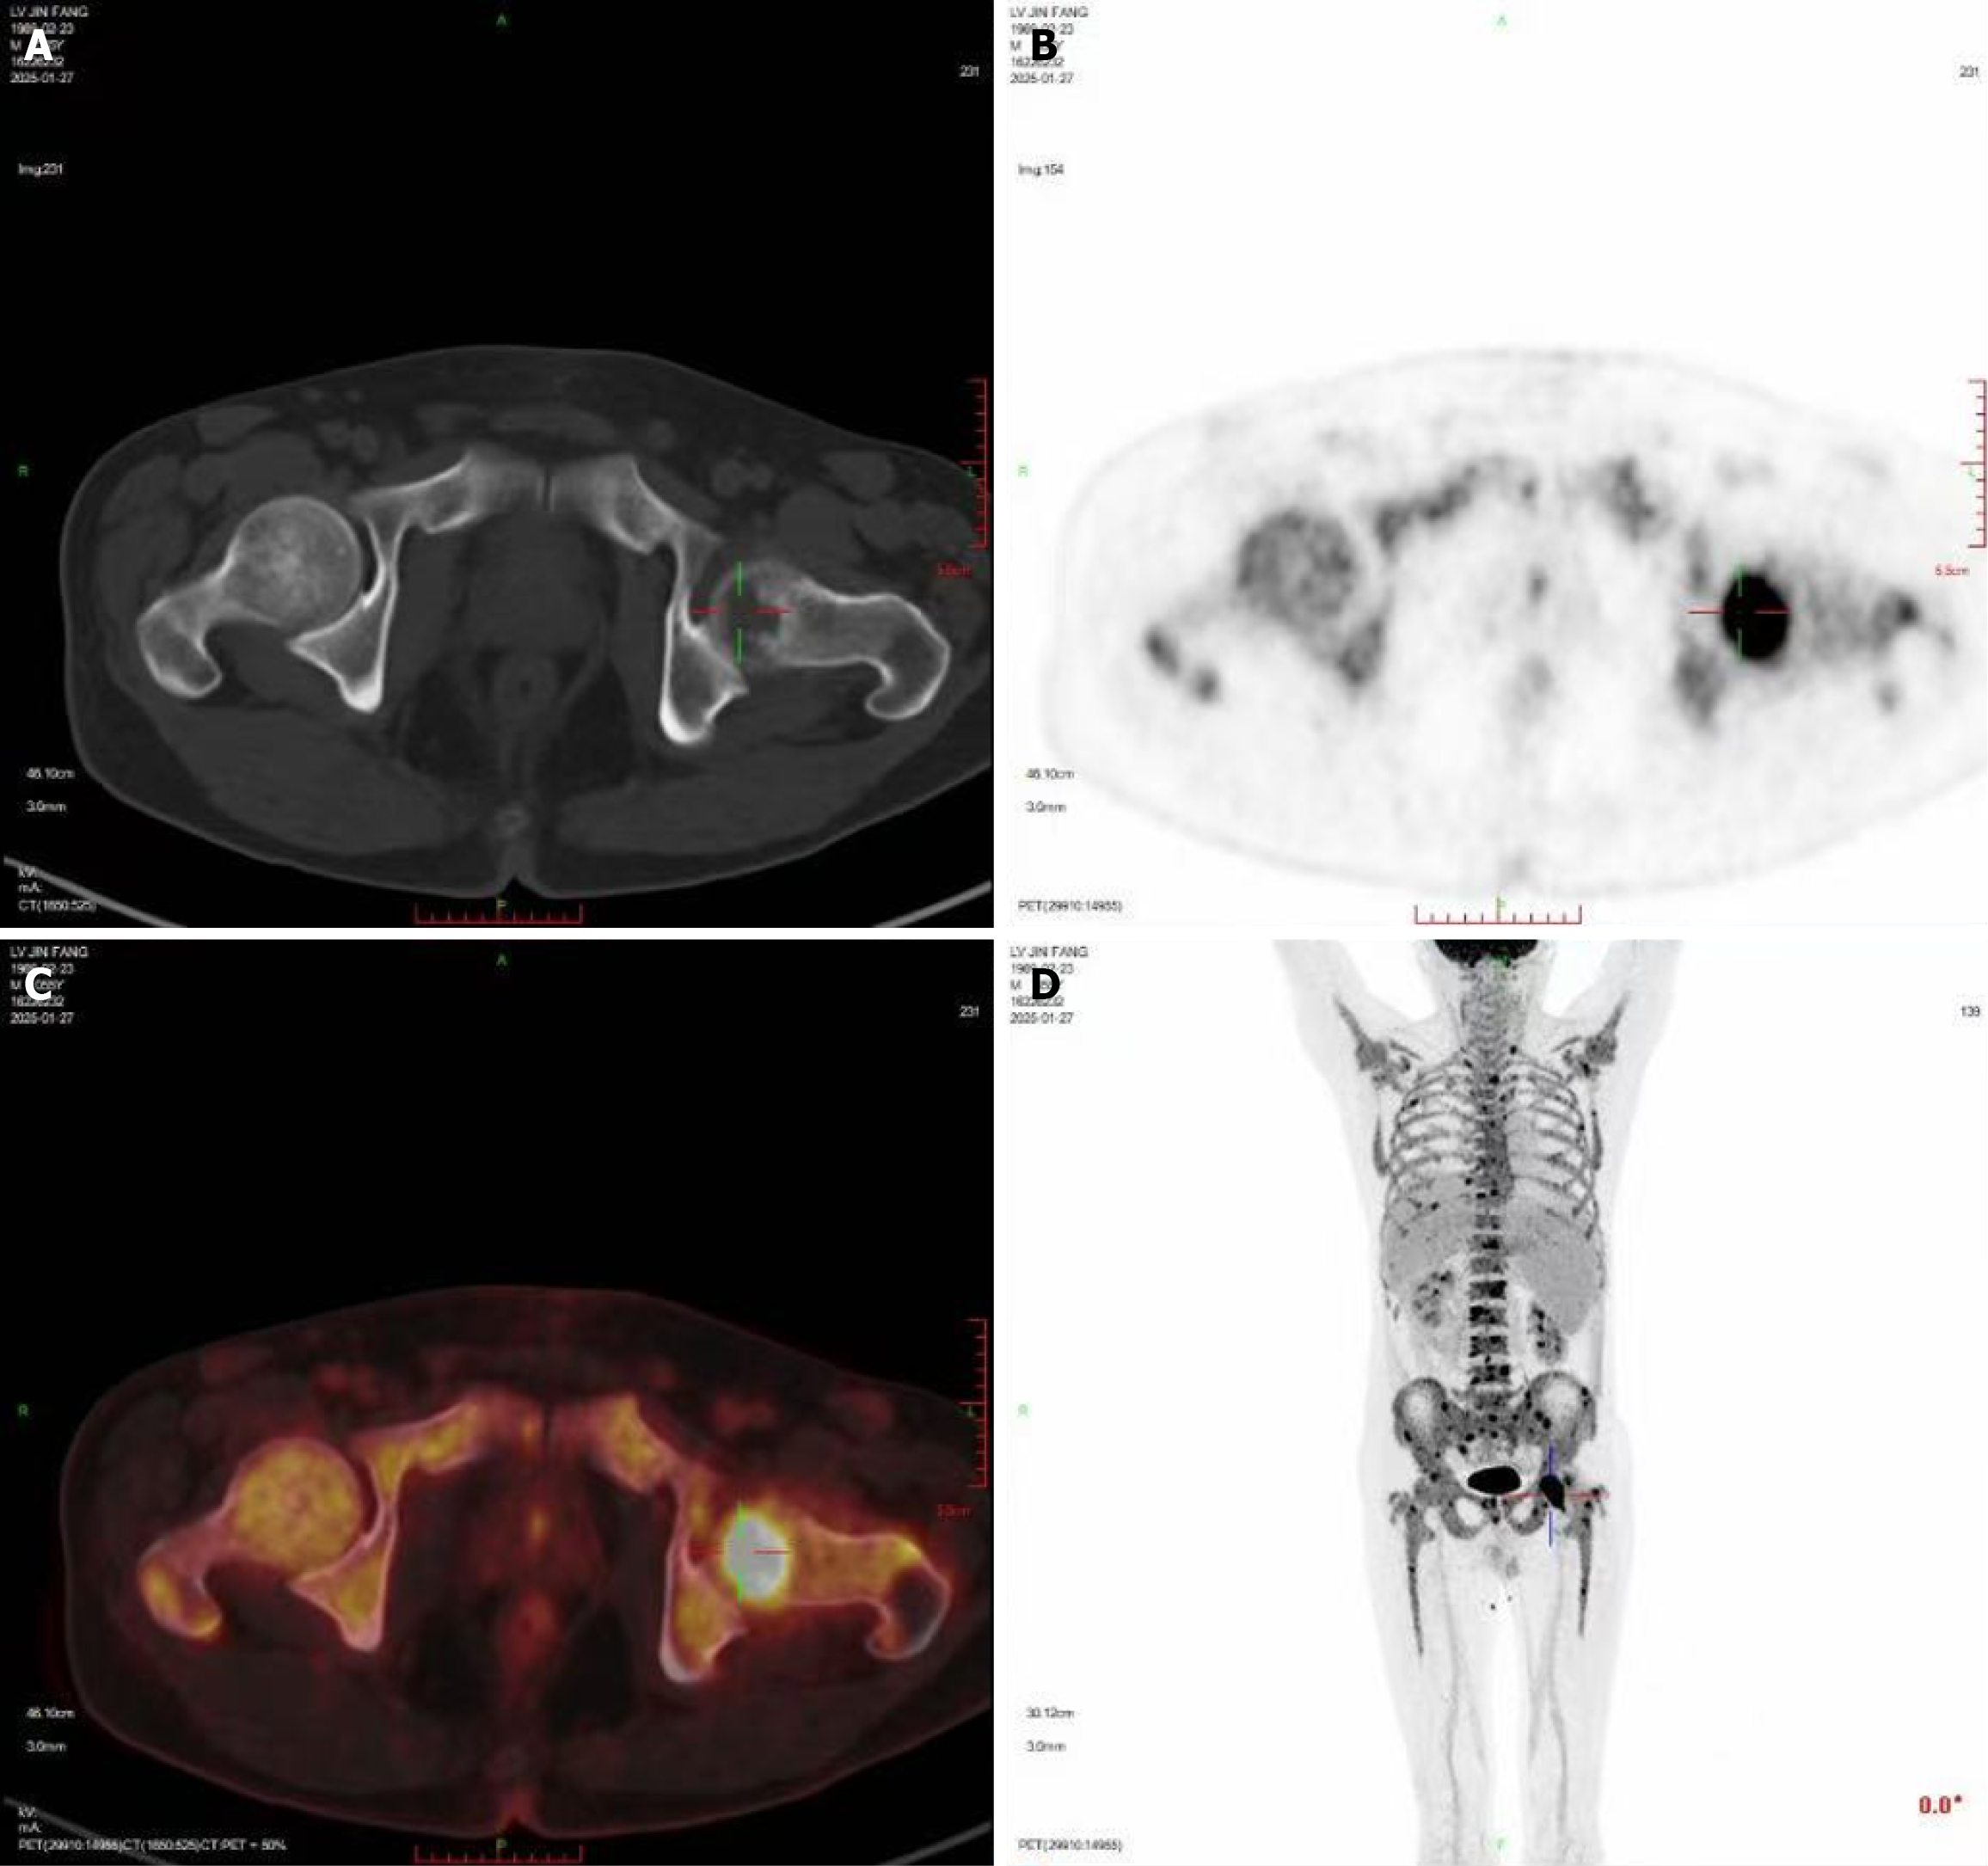

Figure 2 18F-fluorodeoxyglucose positron emission tomography/and computed tomography showing multiple focal bone destructions, mainly in the left femoral head.

A: Non-enhanced computed tomography (CT) image; B: Positron emission tomography (PET) image; C: Fused PET and CT images; D: PET maximal intensity projection image in the coronal plane.